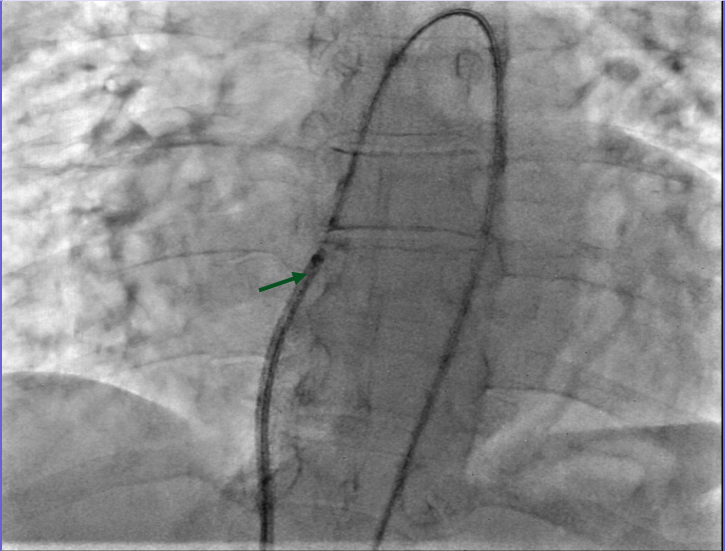

A 7 French delivery sheath was traversed across the ruptured sinus, through the inferior vena cava, to the aorta (Figure 3, Video 3).

Figure 3. Advancement of a 7 French (F) sheath (green arrow) across the arteriovenous (AV) rail.

5. A 7 French delivery sheath was introduced through the venous access site and advanced over the wire across the ruptured SVA.